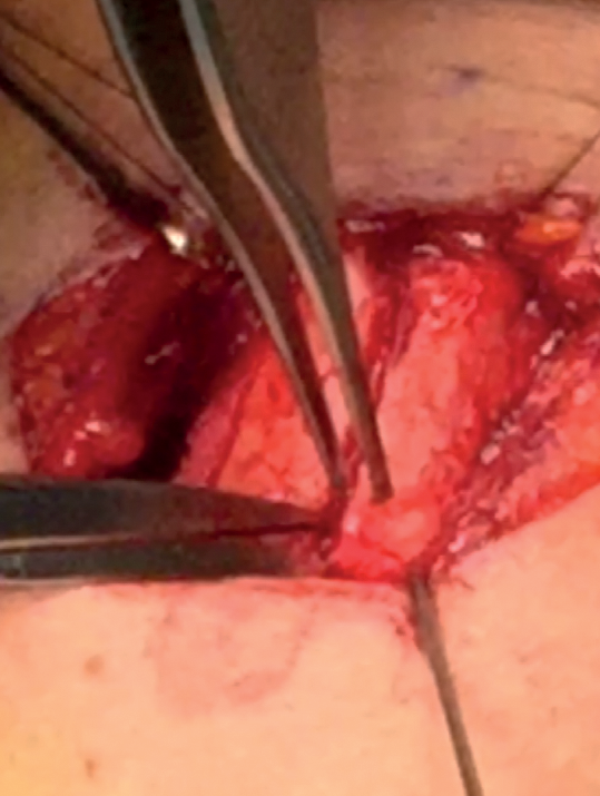

Drilling

Drill the midline fissure using a 1mm fissure burr from superior to inferior and deep by 60% of the depth of the cartilage (Figure 11).

Figure 11: Drilling.